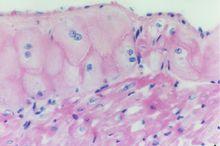

蒲肯野纖維也稱為束細胞,是一種特殊的心肌纖維。屬心臟傳導系統的組成成分,組成房室束及其分支,分布於心室的心內膜下層。其形態特點是:較普通心肌細胞短而寬,胞質中有豐富的線粒體和糖原,而肌原纖維較少,且多位於細胞周邊,故在HE染色的切片中其胞質著色較普通心肌細胞淺。細胞間的連線結構較多,閏盤較多見。房室束分支末端的蒲肯野纖維與普通心室肌纖維相連線,將衝動傳至心室各處。